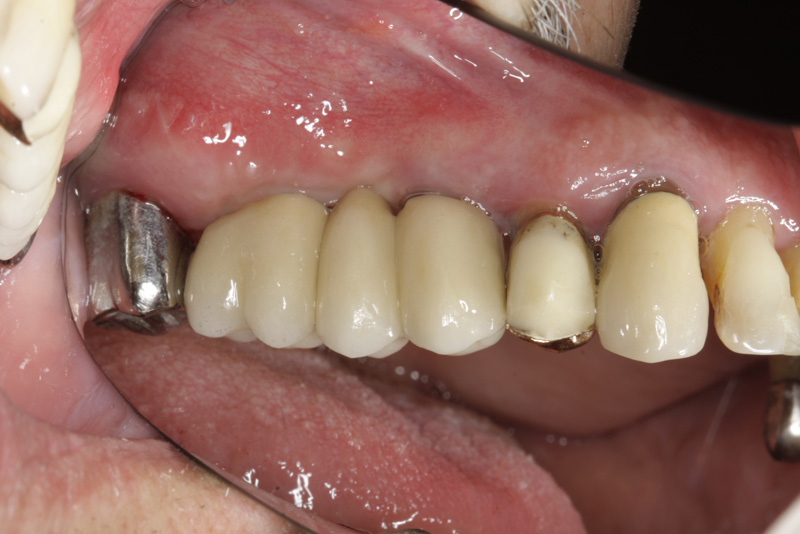

Protetické řešení může být pomocí můstku, který je kotvený na implantátech nebo pomocí jednotlivých korunek na implantátech.

V zásadě je možné do těchto můstků zařadit i přirozené zuby, zejména pokud je potřeba tyto zuby ošetřit proteticky - korunkami. Korunky nebo můstky mohou být na implantáty nacementovány nebo přišroubovány.

Zdravé zuby zůstanou zachovány a přitom náhrady jsou pevné, jako na vlastních zubech